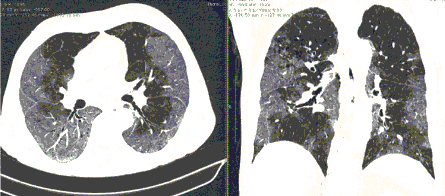

4.3. ЛУЧЕВАЯ ДИАГНОСТИКА COVID-19

Методы лучевой диагностики применяют для выявления COVID-19 пневмоний, их осложнений, дифференциальной диагностики с другими заболеваниями легких, а также для определения степени выраженности и динамики изменений, оценки эффективности проводимой терапии.

К методам лучевой диагностики патологии ОГК пациентов с предполагаемой/установленной COVID-19 пневмонией относят:

- Компьютерную томографию легких (КТ),

КТ имеет высокую чувствительность в выявлении изменений в легких, характерных для COVID-19. Применение КТ целесообразно для первичной оценки состояния ОГК у пациентов с тяжелыми прогрессирующими формами заболевания, а также для дифференциальной диагностики выявленных изменений и оценки динамики процесса. КТ позволяет выявить характерные изменения в легких у пациентов с COVID-19 еще до появления положительных лабораторных тестов на инфекцию с помощью МАНК. В то же время, КТ выявляет изменения легких у значительного числа пациентов с бессимптомной и легкой формами заболевания, которым не требуется госпитализация. Результаты КТ в этих случаях не влияют на тактику лечения и прогноз заболевания при наличии лабораторного подтверждения COVID-19. Поэтому массовое применение КТ для скрининга асимптомных и легких форм болезни не рекомендуется. При первичном обращении пациента с подозрением на COVID-19 рекомендуется назначать КТ только при наличии клинических и инструментальных признаков дыхательной недостаточности (SpO2 < 95%, ЧДД > 22).

3. Применение лучевых методов у пациентов с симптомами ОРВИ легкой степени тяжести и стабильном состоянии пациента, возможно только по конкретным клиническим показаниям, в том числе при наличии факторов риска, при условии достаточных технических и организационных возможностей. Методом выбора в этом случае является КТ легких по стандартному протоколу без внутривенного контрастирования или РГ при ограниченной доступности КТ. Использование УЗИ в этих случаях нецелесообразно. Применение КТ исследования в сроки ранее 3 - 5 дней с момента появления симптомов заболевания, а также при отсутствии клинических проявлений поражения бронхолегочной системы является нецелесообразным. Выполнение КТ целесообразно при наличии клинических и инструментальных признаков дыхательной недостаточности (SpO2 < 95%, ЧДД > 22), либо при дифференциальной диагностике с другим заболеванием.

4. Все выявляемые при лучевых исследованиях признаки, включая КТ-симптомы, не являются специфичными для какого-либо вида инфекции и не позволяют установить этиологический диагноз. Вне клинической (эпидемической) ситуации они не позволяют отнести выявленные изменения к пневмонии COVID-19 и дифференцировать их с другими пневмониями и невоспалительными заболеваниями. Данные лучевого исследования не заменяют результаты обследования на РНК SARS-CoV-2. Отсутствие изменений при КТ не исключает наличие COVID-19 и возможность развития пневмонии после проведения исследования.

9. Оценка динамики течения выявленной пневмонии COVID-19 проводится по клиническим показаниям с применением следующих методов визуализации:

- оптимально: выполнение КТ исследования легких по стандартному протоколу без внутривенного контрастирования;

Комментарии. Кратность повторения КТ, РГ или УЗИ зависит от клинических показаний, диктующих необходимость оценки динамики. Рекомендуемая кратность повторения для КТ и РГ не чаще, чем один раз в 7 дней.